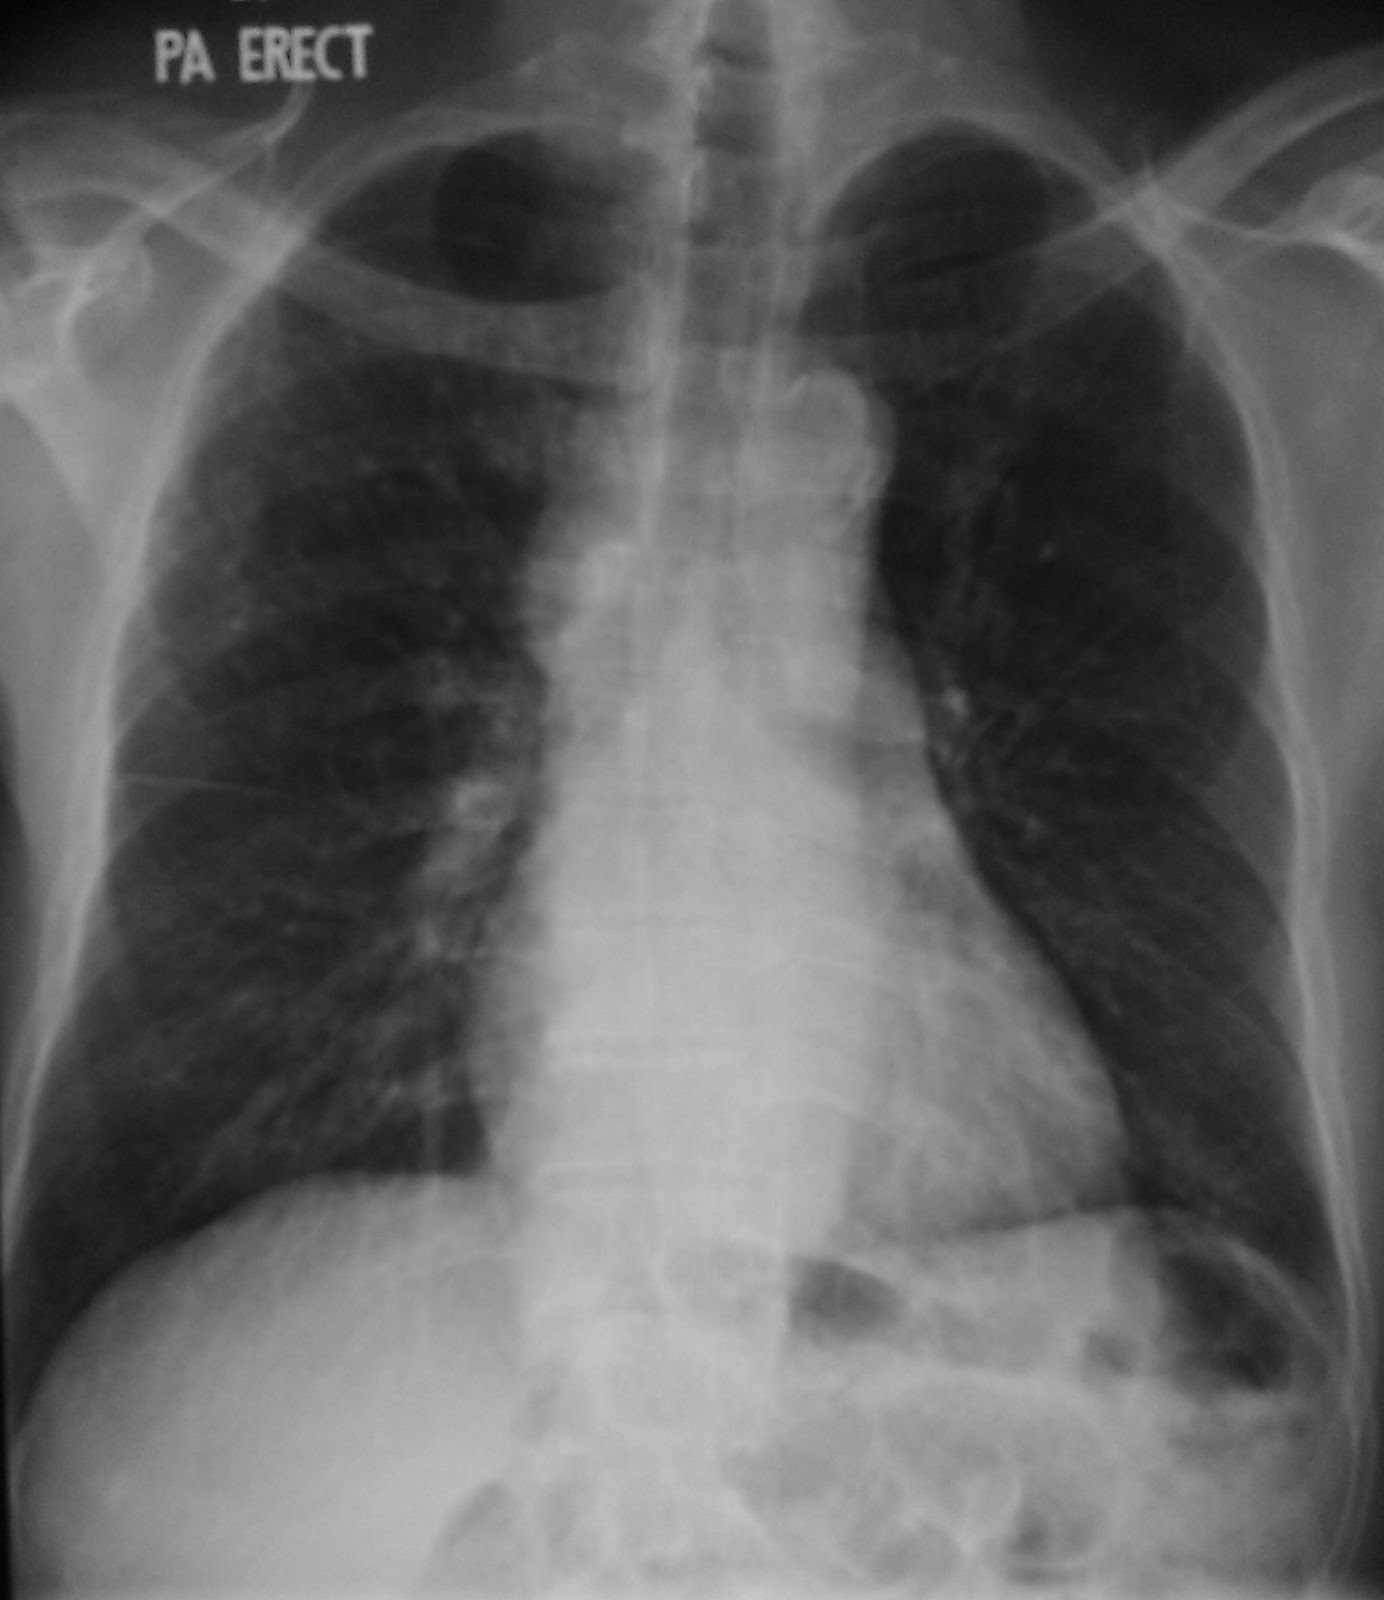

From wikidoc.org

Thymic carcinoma chest x ray wikidoc Thymic Carcinoma Stage 4B thymus cancer ranges from stages i (1) through iv (4). there are 5 stages: (intrathoracic lymph nodes) or to lymph nodes in the. Early detection, diagnosis, and staging. The stage provides a common way of describing the cancer,. stage 4a means the cancer has spread widely into the lining of the lungs (pleura) and the covering layer. Thymic Carcinoma Stage 4B.